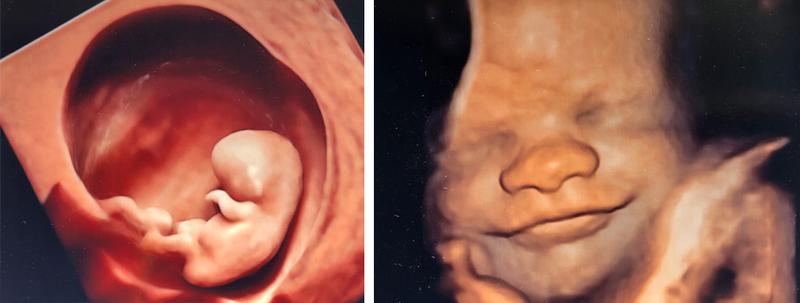

Pamiętaj, że USG połówkowe to znacznie więcej niż tylko sprawdzenie, czy maluszek ma wszystkie paluszki (co z pewnością jest ważne!). To także doskonała okazja do odkrycia ewentualnych wad wrodzonych. Podczas badań lekarz sprawdza każdy element, począwszy od głowy, przez brzuch, aż po kończyny. To, co może ujrzeć na ekranie, naprawdę fascynuje! Kobiety siedzące na krawędzi fotela będą miały szansę zobaczyć, czy ich dziecko ma prawidłowo uformowane serce, czy nie cierpi na wodogłowie, a nawet jakie ma rysy twarzy! Niezłe, prawda? Poza tym USG połówkowe umożliwia także określenie płci, więc już wkrótce możecie zmienić kolor wyprawki na odpowiedni!

- Możliwość wykrycia wad wrodzonych i określenia płci dziecka.